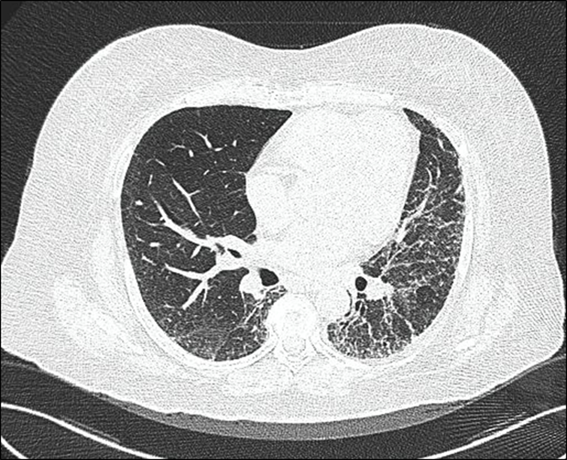

Durante la estancia hospitalaria, se verifica en reiteradas veces fenómeno de Raynaud, y no se evidencian otras lesiones cutáneas. Las manos de la paciente tampoco mostraron lesiones distinguibles o características (figura 3). Se realizó radiografía contrastada del tubo digestivo (figura 4) y se demostró retardo en el vaciamiento en niveles superiores (esófago y estómago), pero no se visualizó dilataciones. Se sometió a capilaroscopía digital, en la que se evidencia hemorragias en astilla en el 3.erdedo de mano izquierda.

Ante la tríada existente (fibrosis pulmonar, afectación digestiva y fenómeno de Raynaud) se hace el diagnóstico probable de una entidadsine. Se solicita estudio de anticuerpos para esclerosis sistémica (anticuerpos anticentromérico -AAC- y antitopoisomerasa -AAT-). El resultado arrojó niveles elevados de AAT. Se concluye en una Esclerosis Sistémicasineesclerodermia (ESse). Se inicia tratamiento con azatioprina 100 mg diarios, manejo que causa intolerancia digestiva, y se cambió a ácido micofenólico (MMF) 2 gramos diarios; además, se indica procinéticos para afectación digestiva.